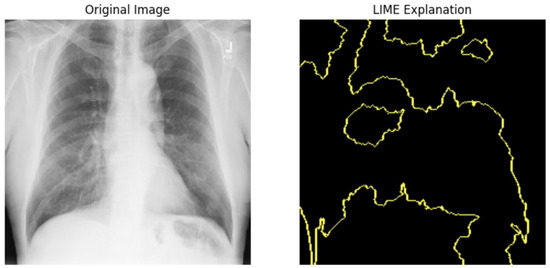

5.4.1. Local Interpretable Model-Agnostic Explanations for Clinical Validation

We applied scientific analysis on a random 7 sample, which was provided by the clinical specialist. The LIME Analysis for Image Data (a), (b), (c), (d), (e), and (f) is in Figure 22, Figure 23, Figure 24, Figure 25, Figure 26 and Figure 27. There are two parts of LIME analysis from the provided chest X-ray images to detect the disease area. Original Image and LIME explanation;

• Original Image: The patient’s thoracic cavity. It displays the typical anatomical structures of the chest, including the lungs, ribs, and heart.

• LIME Explanation: The result of applying LIME to the chest X-ray image. The yellow boundaries indicate the regions of the image that were most influential in the model’s decision-making process when determining whether the image indicated a particular condition. In this context, these regions are the parts of the X-ray that the AI model considered most important for making its diagnostic prediction.

The analysis very useful for clinicians to understand the model’s behavior and ensure that it aligns with medical expertise. The use of LIME helps in making the AI model’s interpretability decisions more transparent and interpretable. It allows medical professionals to verify whether the AI’s focus areas correspond to clinically significant regions. It also enhanced diagnostic capability of understanding which parts of the images in the AI model in refining the model further and ensures that it makes accurate and reliable predictions. This is particularly crucial in medical diagnostics where interpretability and accuracy are paramount.

Figure 24. LIME Analysis for Image Data (c) on original image to LIME explanation.

Jpm 14 00856 g024